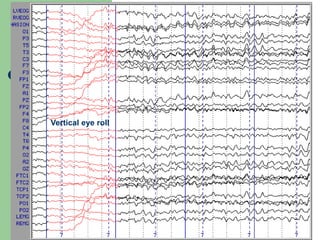

Vertical eye roll